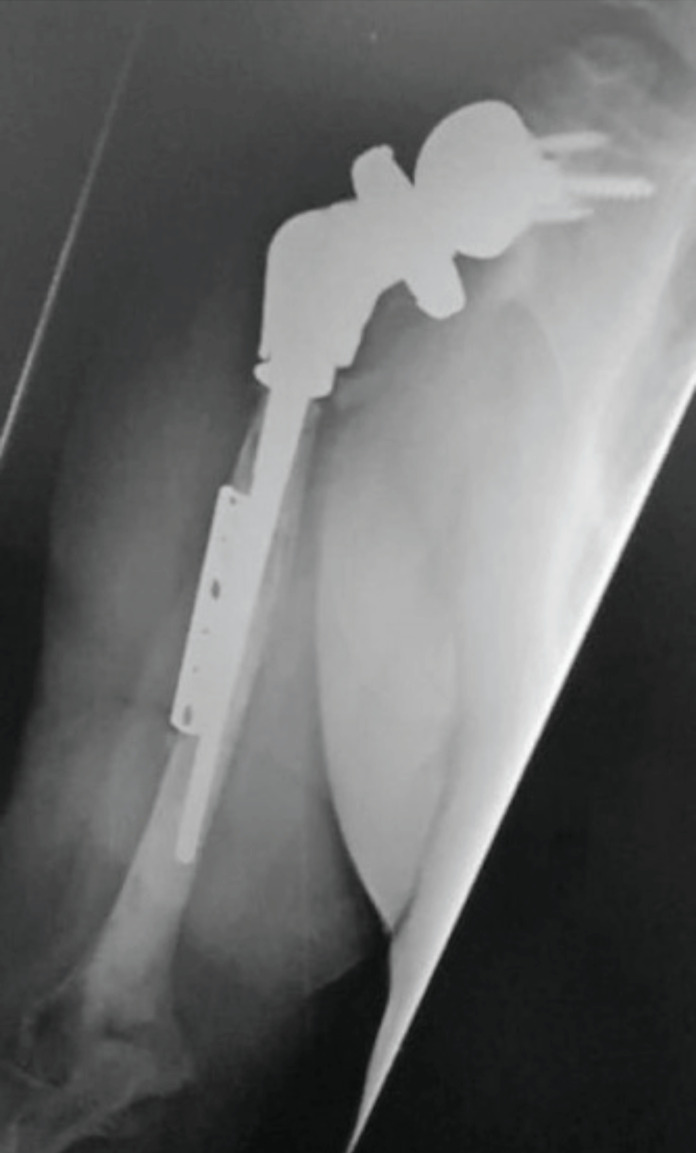

Abstract Image

Results: A total of 32 patients were identified with a mean age of 67.64 years and the most common cause of revision was a combination of bone and soft tissue failure (39.3%). All patients (n=8) with hemiarthroplasty had rotator cuff deficiency while patients with resurfacing had both rotator cuff failure and bony erosion. Four patients needed a proximal humeral osteotomy and six patients needed allograft reconstruction of the glenoid for bone loss. Twenty-one shoulders were revised to reverse total shoulder arthroplasty (TSA), 2 to anatomical TSA and 5 were left with cement spacer in situ. Mean duration of follow-up was 41.6 months. Mean OSS at the last follow-up was 26.88 with statistically significant improvement in ROM. There was no statistical difference in clinical outcomes (p>0.05) based on the type of primary prosthesis or cause of revision. A total of 70% patients were pain free. Patients with infection had inferior outcomes with a mean OSS of 17.